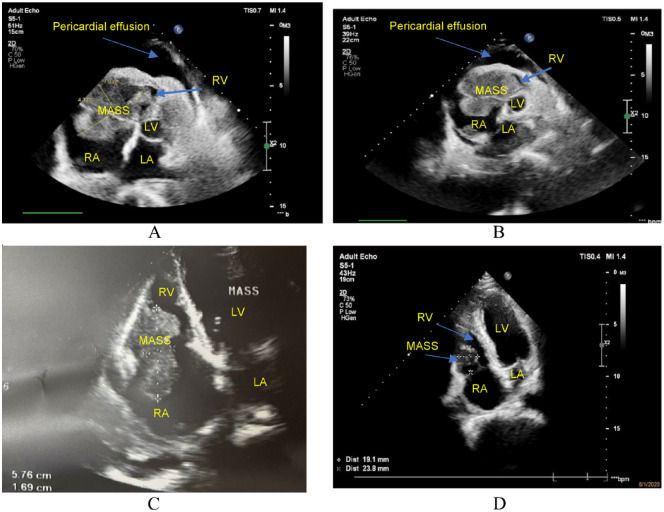

Heart tumors are sporadic. Secondary heart tumors are 30 times more common than primary ones. Depending on the location and origin of the tumor, clinical pictures vary from asymptomatic to severe manifestations such as arrhythmia, heart failure, pericardial effusion, and cardiogenic shock. We report hereby a rare case who presented with faint clinical symptoms, rapidly progressing to right heart failure within a month. Echocardiography and computed tomography of the chest revealed a tumor in the right heart chamber of 72.0 × 43.0 mm, in addition to large mediastinal lymph and left supraclavicular lymph nodes, cardiogenic shock appeared 4 days after admission. Through examination, it was suspected that this was a cardiac lymphoma. The patient was treated with 2 mg methylprednisolone per kg body weight. Symptoms of cardiogenic shock improved significantly and disappeared after 6 hours of treatment. After supraclavicular lymph node biopsy and immunohistochemistry, the final result was diagnosed as diffuse large B-cell non-Hodgkin lymphoma with large lymphoma in the right heart. The patient received chemotherapy with the R-CHOP regimen (Rituximab, Cyclophosphamide, Doxorubicin, Vincristine, and Prednisolone). Re-examination before the 5th chemotherapy cycle showed no signs of right heart failure, normal self-activity, and no dyspnea on exertion, and the tumor size in the heart on the echocardiogram was 23.8 × 19.1 mm. The report shows that a large right heart tumor with a clinical picture of cardiogenic shock in a patient with diffuse large B-cell non-Hodgkin's lymphoma was well-responded to initial treatment with methylprednisolone at a dose of 2 mg/kg body weight and R-CHOP chemotherapy.